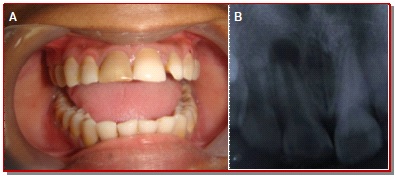

In the present study, the ability of mineral trioxide aggregate in the formation of apical plug for healing of large periapical lesion with open apex was assessed and evaluated the clinical outcome. Fifteen participants with periapical lesion at the upper anterior teeth with open apex were treated with mineral trioxide aggregate. The effect on healing of apical size was evaluated at 3, 6, and 12 months by radiological examinations in the form of periapical index criteria, diameter of the lesion size and the presence or absence of apical tissue barrier. The results found that neither pain nor any sinus was detected at 12 months. The mean size of the apical lesion was gradually reduced from 5.1 × 3.8 to 1.5 × 0.9 mm and mean PAI was reduced from 3.3 to 1.7 mm. The differences between mean size of periapical lesion at preoperative and 12 months observation period was also statistically significant (p<0.05). The clinical success shown significant success rate of 93.3% analyzed with Z-test. In conclusion, tooth with open apex can be successfully treated with mineral trioxide aggregate apexification technique followed by root canal obturation.